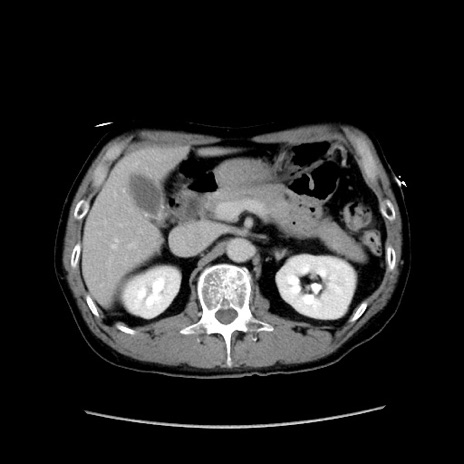

冠状断像

【症例】40歳代 男性

【主訴】腹痛

【現病歴】4時間ほど前に電車に乗車中に臍部上より腹痛出現。徐々に増悪し起立困難となり、救急外来受診。生ものは数日食べていない。今朝お雑煮を食べた。

【身体所見】BT 36.8℃、BP 117/84mmHg、HR 91/min、SpO2 97%、苦悶様、腹部:臍上部広範囲圧痛あり、反跳痛±

【データ】WBC 8100、CRP 0.03